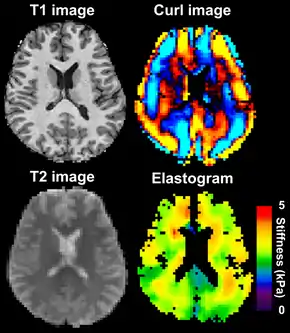

MRE is conducted in three steps: first, a mechanical vibrator is used on the surface of the patient's body to generate shear waves that travel into the patient's deeper tissues; second, an MRI acquisition sequence measures the propagation and velocity of the waves; and finally this information is processed by an inversion algorithm to quantitatively infer and map tissue stiffness in 3-D.[2][3] This stiffness map is called an elastogram, and is the final output of MRE, along with conventional 3-D MRI images as shown on the right.[2]

Magnetic resonance elastography of the brain. A T1 weighted anatomical image is shown in the top-left, and the corresponding T2 weighted image from the MRE data is shown in the bottom-left. The wave image used to make the elastogram is shown in the top-right, and the resulting elastogram is in the bottom-right. | |

MRE of the brain [27] was first presented in the early 2000s.[28][29] Elastogram measures have been correlated with memory tasks,[30] fitness measures,[31] and progression of various neurodegenerative conditions.[27] For example, regional and global decreases in brain viscoelasticity have been observed in Alzheimer’s disease[32][33] and multiple sclerosis.[34][35] It has been found that as the brain ages, it loses its viscoelastic integrity due to degeneration of neurons and oligodendrocytes.[36][37] A recent study looked into both the isotropic and anisotropic stiffness in brain and found a correlation between the two and with age, particularly in gray matter.[38]